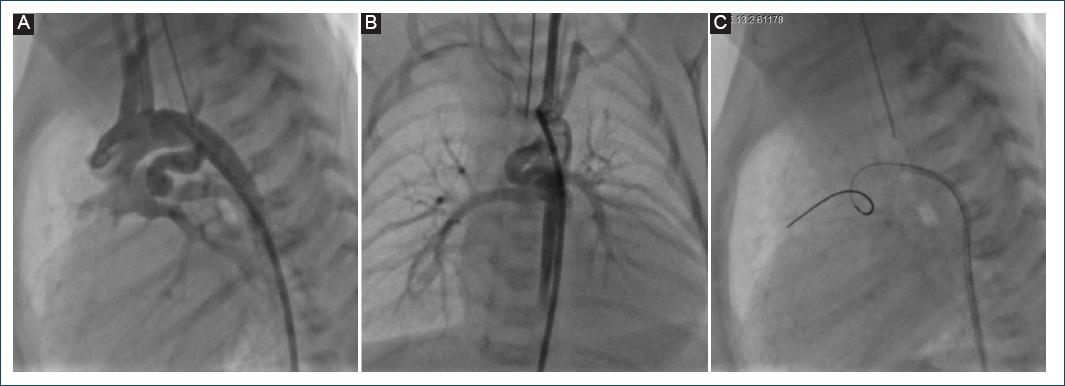

Figura 3 A y B: angiografía de arco aórtico que muestra un conducto arterioso tipo 3 (muy tortuoso) que hace un asa de 360°, cerca del extremo pulmonar. C: se cruza una guía de angioplastia coronaria de 0.014 pulgadas a través del conducto arterioso.

Dadas las ventajas del StD demostradas en este y otros estudios previos, vale la pena comentar que existen recomendaciones en relación al tipo de CA candidato a la colocación de StD. Se ha mencionado que los CA muy tortuosos (tipo 3) no son candidatos a la colocación de StD, pero en la mayoría de nuestros casos (excepto en dos) fue posible colocarlo de manera exitosa independientemente de la anatomía ductal, incluso en aquellos con un CA tipo 3, como se muestra en las figuras 3 y 4.